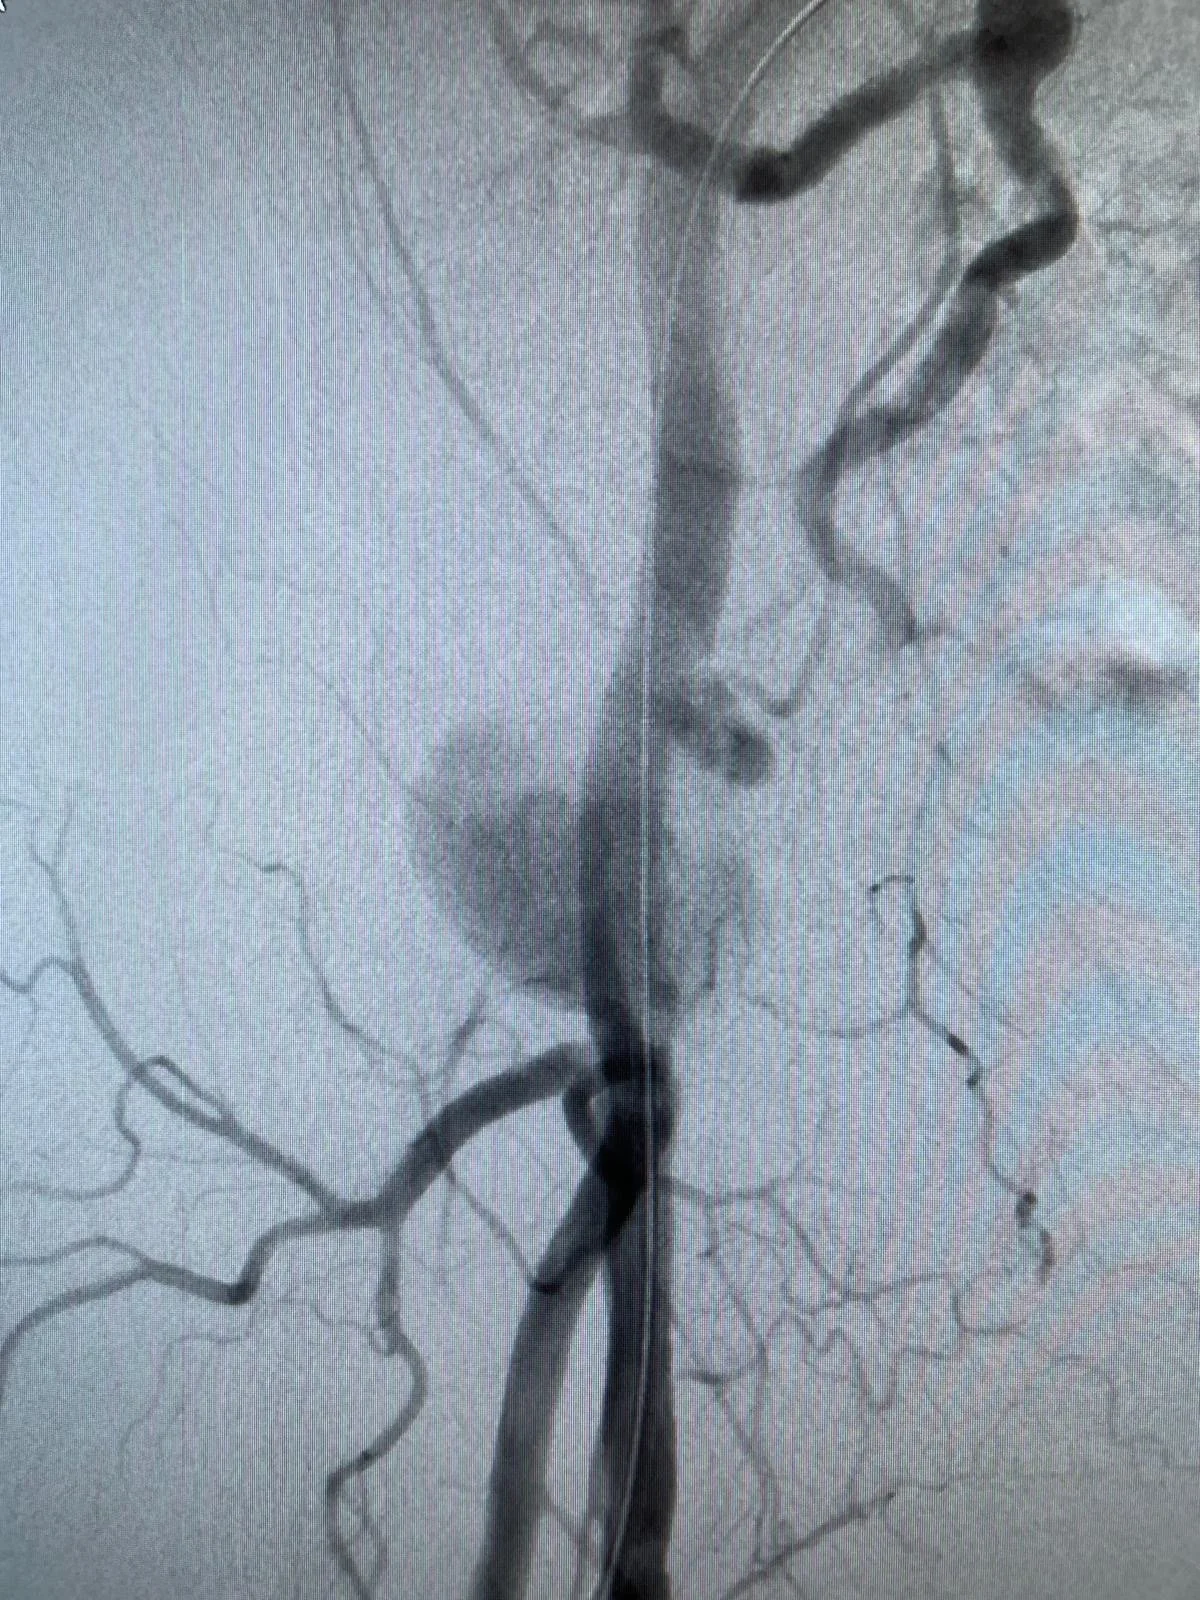

• Minimal-invasive Eingriffe bei der Aorta (EVAR, FEVAR, TEVAR)

Ich bin ein anerkannter Facharzt für Herz- und thorakale Gefässchirurgie sowie Chirurgie mit Schwerpunkt Aortenchirurgie & komplexer Gefässchirurgie. Mit umfassender internationaler Erfahrung, unter anderem als Consultant Vascular Surgeon am Guy’s and St. Thomas’ NHS Trust in London und als Chef de Clinique an der CHU Bichat-Claude Bernard in Paris, biete ich modernste gefässchirurgische Behandlungen auf höchstem Niveau. Meine Expertise umfasst minimal-invasive endovaskuläre Verfahren, komplexe Aortenchirurgie, Karotis-Chirurgie sowie venöse Eingriffe. Ich bin Mitglied der FMH und verfügt über Zusatzausbildungen wie Phlebologie (USGG) und Endovenöse thermische Ablation.